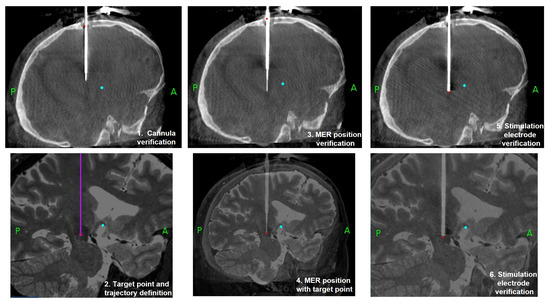

2. Materials and Methods